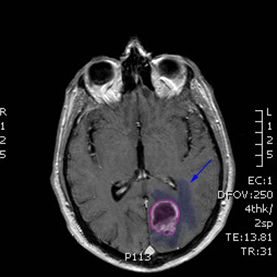

Όγκος εγκεφάλου με περιβάλλον οίδημα. |